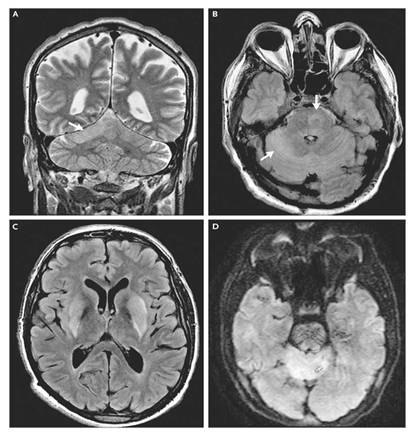

Hình 1